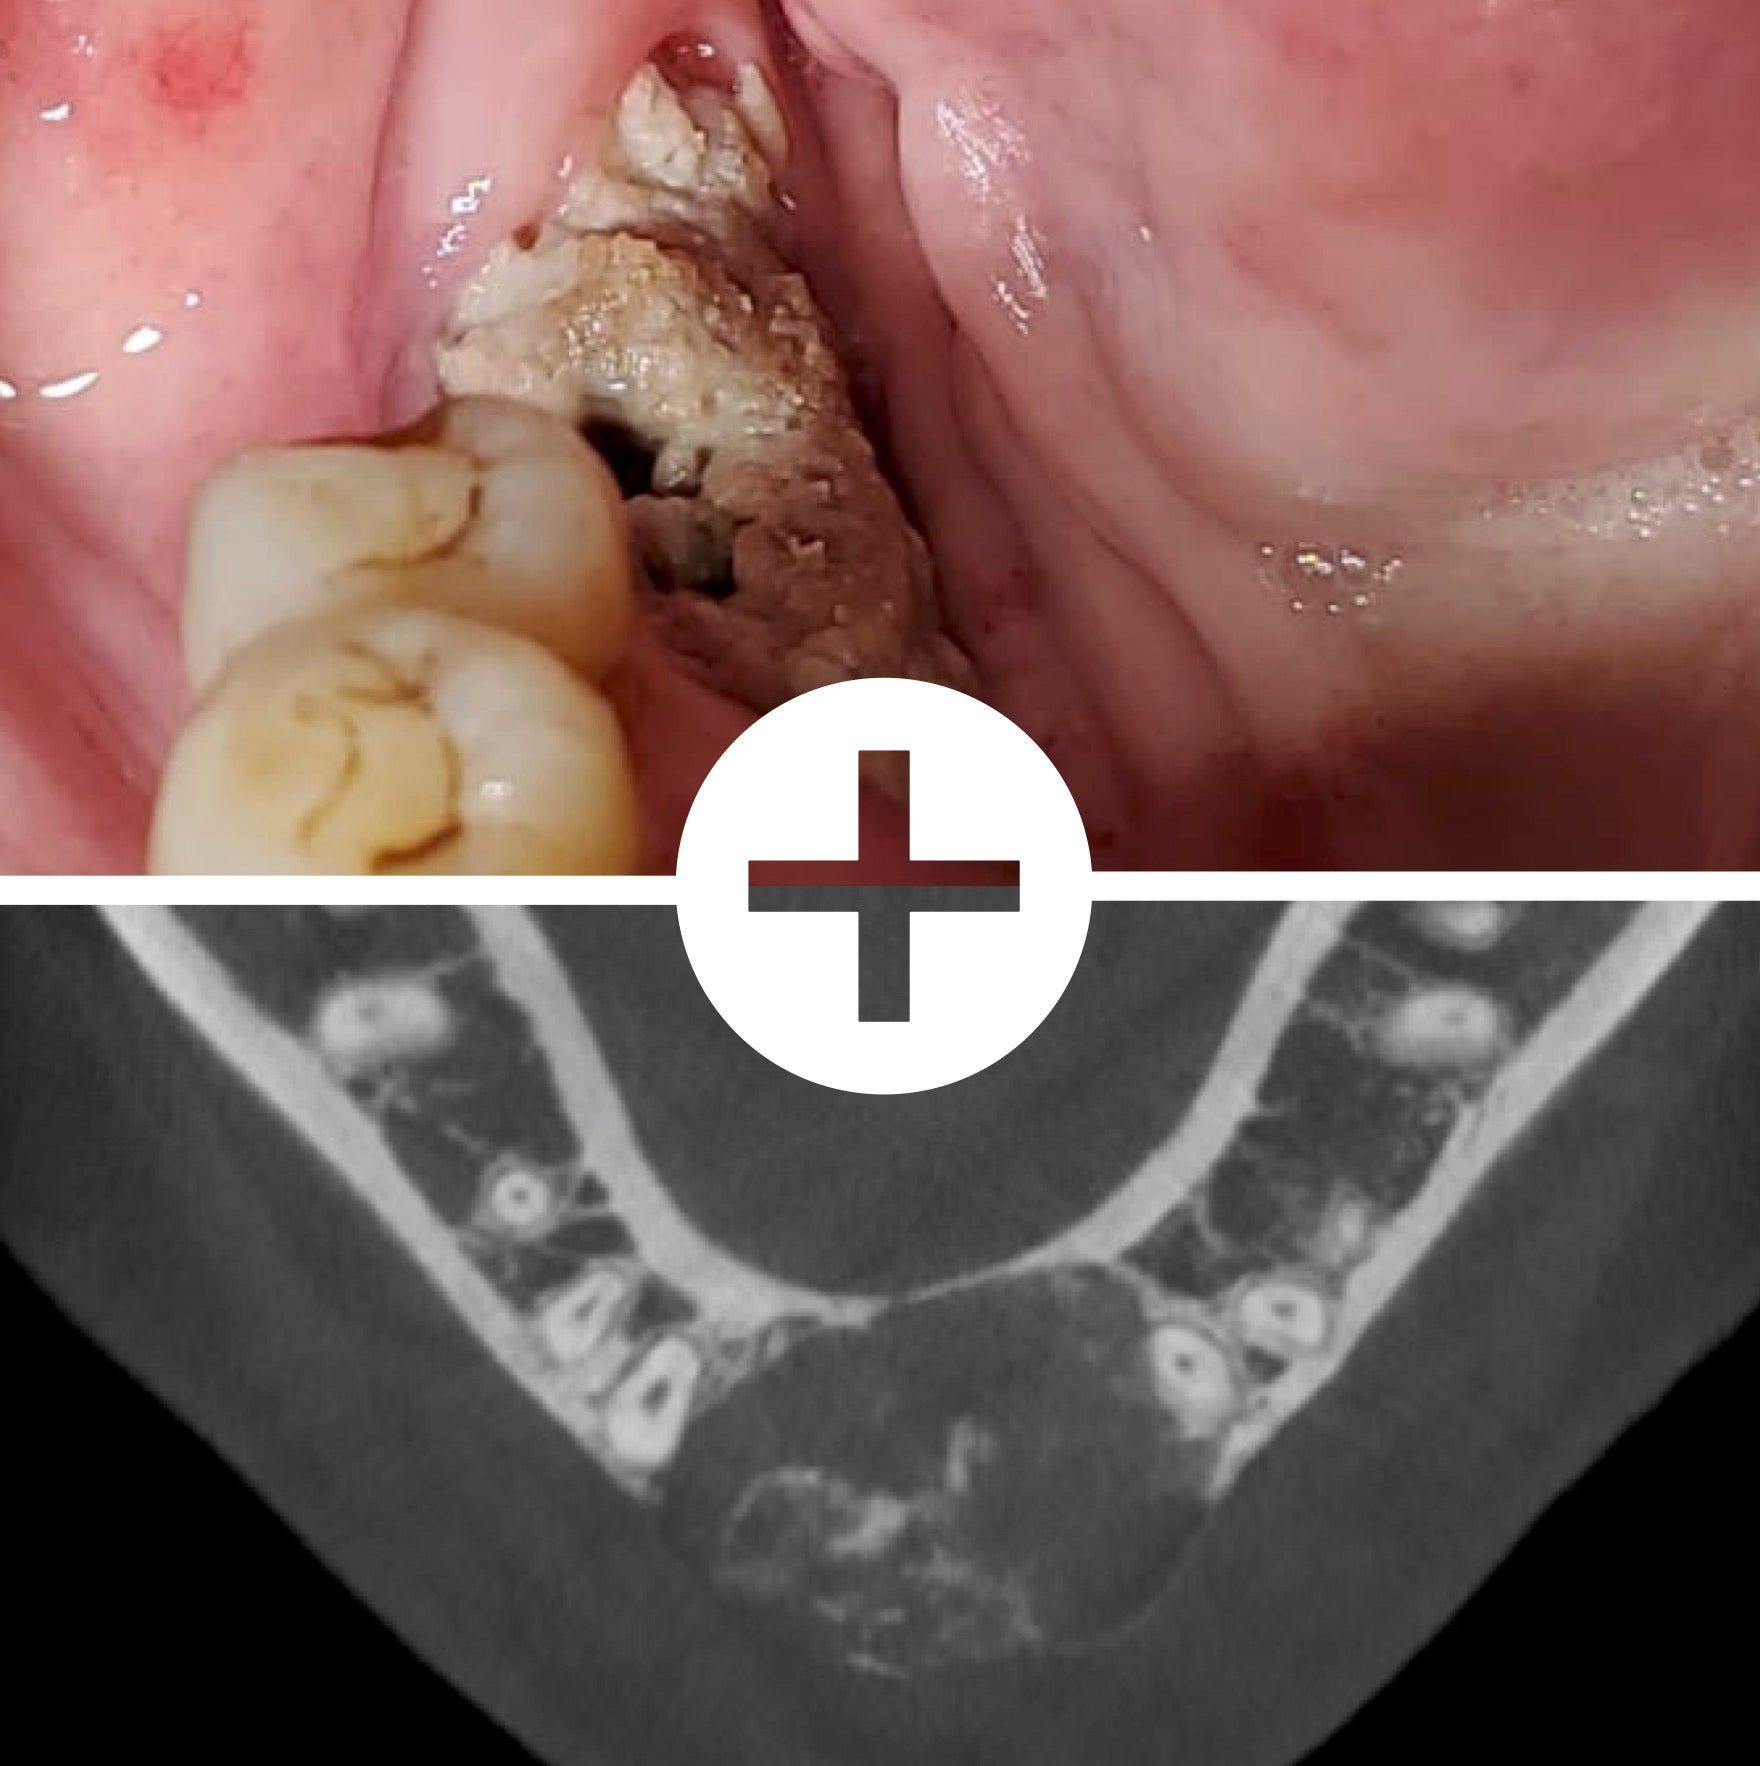

La dermatologie buccale constitue un domaine essentiel mais souvent sous-exploité de la pratique odontologique. La cavité buccale peut révéler de nombreuses lésions muqueuses , bénignes ou éventuellement malignes, d'origine locale ou systémique.

Face à la diversité des manifestations cliniques (ulcérations, leucoplasies, érythèmes, lésions pigmentées, douleurs muqueuses, etc.), le chirurgien-dentiste joue un rôle clé dans le dépistage, le diagnostic précoce et l'orientation thérapeutique .